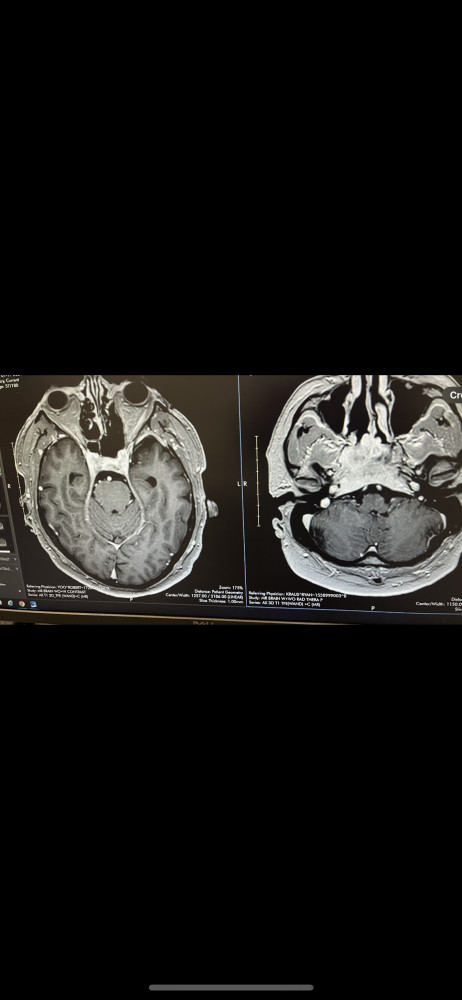

This is my MRI when the doctor found the tumor on September 2023 and November of 2024

I'm a 60 y.o. guy. In September 2013, I started having horrible headaches and started seeing double. After 5 doctors looking and treating for the wrong illness, I finally found the right doctor, and he diagnosed me with brain cancer. I was hospitalized for 7 days. I had a biopsy done, and doctors found out my tumor was malignant and inoperable.